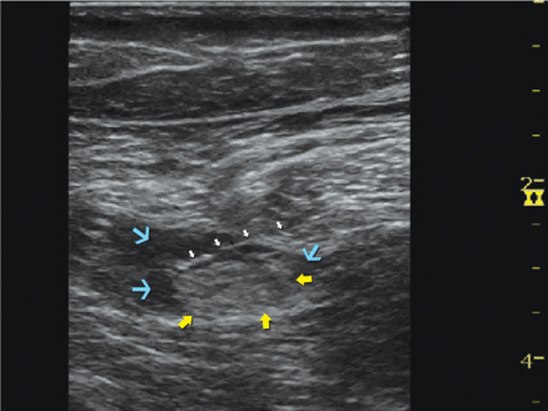

The description of the technique in this chapter will focus primarily on the transgluteal approach. However, since the subgluteal approach is performed just a few centimeters more distal and it is technically easier, the reader can easily perform either approach by using general guidelines provided and referring to Figure 39.2-3, Figure 39.2-4, and algorithms at the end of the chapter. With the patient in the described position, the skin is disinfected and the transducer is positioned so as to identify the sciatic nerve (Figure 39.2-4). If the nerve is not immediately apparent, tilting the transducer proximally or distally can help improve the contrast and bring the nerve “out” of the background of the musculature. Often, the nerve is much better imaged after the injection of local anesthetic (Figure 39.2-5). Alternatively, sliding the transducer slightly proximally or distally can improve the quality of the image and allow for better visualization. Once identified, the needle is inserted in-plane, typically from the lateral aspect of the transducer and advanced toward the sciatic nerve. If nerve stimulation is used (1.0 mA, 0.1 msec), the passage of the needle through the anterior fascial plane of the gluteus muscles often is associated with a motor response of the calf or foot. Once the needle tip is positioned adjacent to the nerve (Figure 39.2-6A) and after careful aspiration to rule out an intravascular needle placement, 1 to 2 mL of local anesthetic is injected to document the proper injection site. Such injection often displaces the sciatic nerve away from the needle; therefore, an additional advancement of the needle 1 to 2 mm toward the nerve may be necessary to ensure the proper spread of the local anesthetic. When injection of the local anesthetic does not appear to result in a spread around the sciatic nerve, additional needle repositions and injections may be necessary. Assuring the absence of high resistance to injection is of utmost importance because the needle tip is difficult to visualize on ultrasound due to the steep angle and depth of the needle placement.

FIGURE 39.2-5. Sciatic nerve (yellow arrows) as seen in the subgluteal position (linear transducer), needle path (white arrows) and local anesthetic (turquoise arrows) in the intramuscular tunnel surrounding the sciatic nerve.